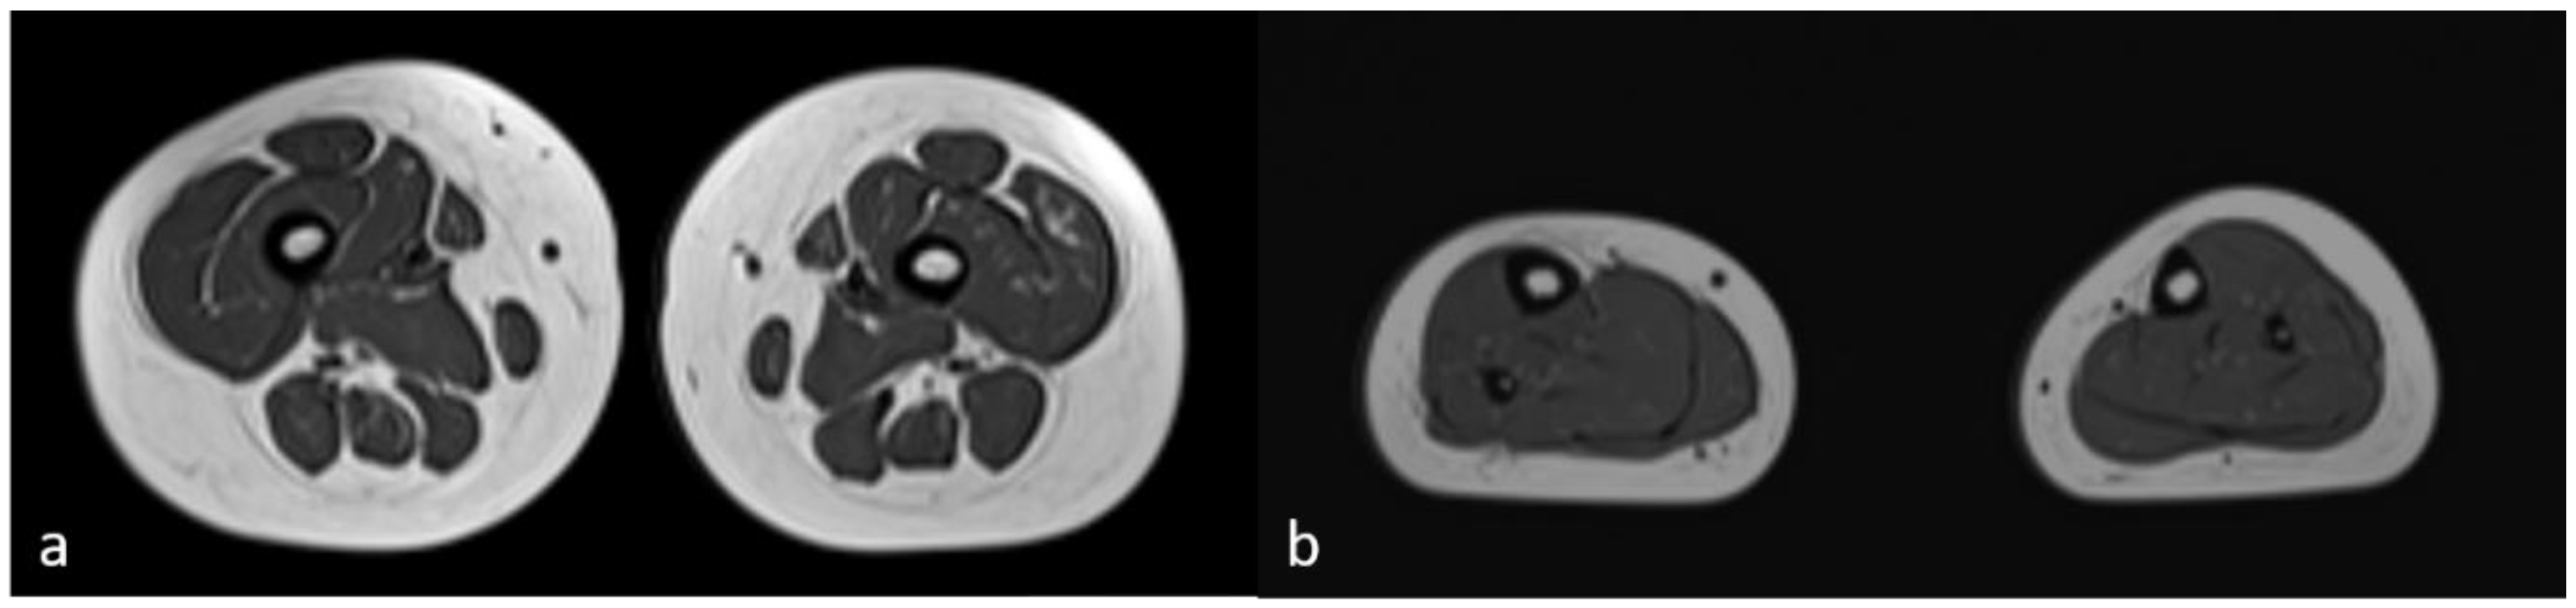

The breakpoint between isodisomy and heterodisomy in 15q was located at chr15:g.60984740 (Table 1, Figure 6, Supplementary Figure S2) in a noncoding region between exon 1 and 2 of RORA (HGNC:10258) gene (NM_134261.3). RORA is associated with intellectual developmental disorder with or without epilepsy or cerebellar ataxia (MIM#618060). There was no deleterious variant identified in RORA, but genomic breakpoints can often affect a genes’ function. Both PWS and RORA phenotypes are associated with seizures, and it was not clear if any potential abnormality of RORA could be contributing to the phenotype in the proband. To account for the possibility of breakpoint affecting the RORA’s function, brain magnetic resonance imaging (MRI) was performed. In individuals with heterozygous RORA loss of function, cerebellar hypoplasia and pontocerebellar atrophy are typically indicated. The evaluation of MRI in the proband was unremarkable (Figure 8). Sagittal T1-weighted image showed normal formation of the corpus callosum and shape and volume of cerebellar vermis and brainstem. The Axial T2-weighted image displays normal white matter myelinization and basal ganglia volumes.

The breakpoint between maternal isodisomy and heterodisomy was located in the noncoding region of the RORA gene. RORA is associated with autosomal dominant intellectual developmental disorder with or without epilepsy or cerebellar ataxia (MIM#618060) [41]. The clinical findings of RORA associated disorder have variable phenotype and include intellectual impairment at varying degrees from normal to severe, speech delay, seizures at multiple types, strabismus, delayed motor development and walking, ataxia, hypotonia, poor coordination and/or mild tremor, hypoplastic cerebellum, and pontocerebellar atrophy [41]. In the proband herein, the phenotypical features expected from RORA associated disorder, namely seizures, developmental delay, speech delay, hypotonia, and broad-based gait overlapped with PWS or calpainopathy phenotypes. However, abnormal RORA is reportedly associated with a distinctive brain MRI pattern of cerebellar hypoplasia and pontocerebellar atrophy in some patients. To date, MRI was unremarkable in our patient as shown Figure 4. Age related penetrance or phenotypic variability may present confounding factors. Future studies are required to examine the potential functional impact of the breakpoint in the RORA gene.

Figure 8. Brain MRI. a) Sagittal T1-weighted image showing complete formation of the corpus callosum and normal shape and volume of cerebellar vermis and brainstem. b) Axial T2-weighted image displays adequate white matter myelinization and normal basal ganglia volumes.